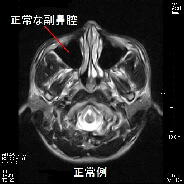

また緑内障など眼科的な問題で慢性的な頭痛を引き起こしている場合もありますし,耳鼻科的疾患である副鼻腔炎(蓄膿症)が原因となっている場合も結構見られます.最近はアレルギー性鼻炎の方が多く2次的に急性副鼻腔炎を引き起こしている方も多く見られます.左の写真は副鼻腔炎の症例ですが,正常例と比較すると膿の貯留により副鼻腔が白くなっています.これらの頭痛も検査をすればすぐに原因が判明します.このように頭痛の原因は思いもよらないところにある場合があり,慢性的な頭痛にお悩みの方は一度検査をお勧めします.